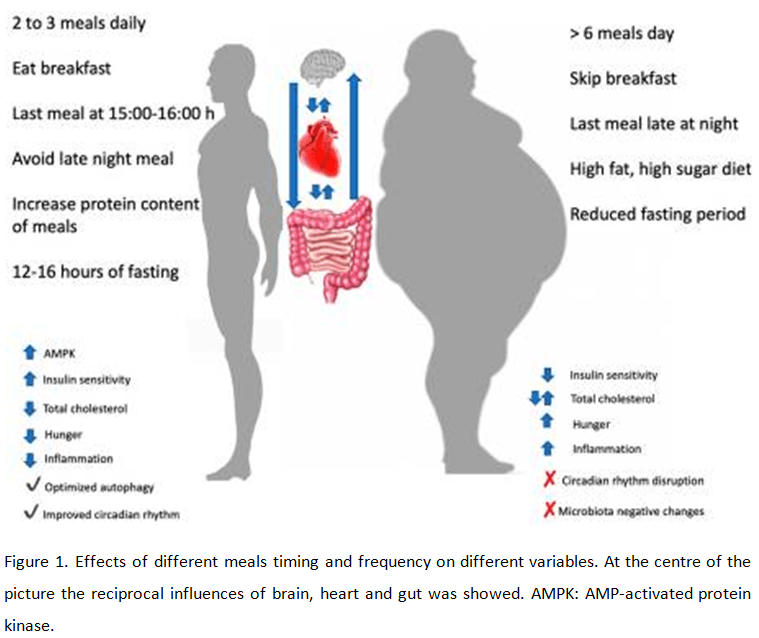

Nutrition affects mutations in genes and can thus change our genome. Nutritional factors can neutralize mutations in genes. Unlike relatively stable genetic information, epigenetic “tags” under certain conditions can be reversible. This fact allows us to rely on a fundamentally new methods of dealing with common diseases, based on eliminating the epigenetic modifications that have emerged in humans under the influence of adverse factors. The use of approaches aimed at correction of the epigenome, opens up great prospects [7, 41, 43]. And in order to fulfill their nutrients function requires the proper functioning of the digestive system, detoxification systems of the liver and intestine. This is the foundation of the basics. (Fig 1.) [8]. We can practically use this data now.

Thus, following the technology developed by Global Longevity, we can now use events to increase life expectancy with the best health and a clear mind and with a beautiful body. This unification and use of all known and available scientific facts that contribute to the maximum quality and longevity longevity (Fig.4).